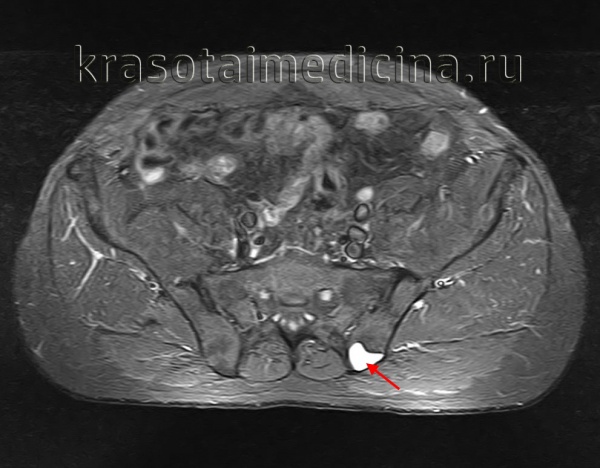

Для диагностики аневризматических костных кист запястья врачи обычно проводят рентгенологическое исследование Рентгенологическое исследование Зачастую врач может диагностировать костно-мышечное заболевание на основании анамнеза и по результатам физикального осмотра. Чтобы облегчить постановку или подтверждение диагноза, иногда необходимы. Прочитайте дополнительные сведенияХирургическое удаление всей кисты является наиболее результативным видом лечения, но иногда наблюдается ее рецидив, особенно при неполном удалении кисты. Лучевой терапии следует по возможности избегать, поскольку в дальнейшем возможно развитие злокачественных опухолей. Однако лучевая терапия Лучевая терапия для лечения онкологического заболевания Радиация является формой интенсивной энергии, генерируемой радиоактивным веществом, таким как кобальт, или специализированным оборудованием, например (линейным) ускорителем атомных частиц. Облучение. Прочитайте дополнительные сведения может быть показана для лечения кист позвоночника, не подлежащих хирургическому лечению и сдавливающих спинной мозг.

Встречается реже солитарной. Обычно возникает у девочек 10-15 лет. Может поражать кости таза и позвонки, реже страдают метафизы длинных трубчатых костей. В отличие от солитарной костной кисты, как правило, возникает после травмы. Формирование полости сопровождается интенсивными болями и прогрессирующим отеком пораженной области. При осмотре выявляется местная гипертермия и расширение подкожных вен. При локализации в костях нижних конечностей отмечается нарушение опоры. Заболевание нередко сопровождается развитием контрактуры близлежащего сустава. При костных кистах в позвонках появляются неврологические нарушения, обусловленные сдавление спинномозговых корешков.

Различают две формы аневризмальных костных кист: центральную и эксцентрическую. В течении болезни выделяют такие же фазы, как и при солитарных кистах. Клинические проявления достигают максимума в фазе остеолиза, постепенно уменьшаются в фазе отграничения и исчезают в фазе восстановления. На рентгенограммах в фазе остеолиза выявляется бесструктурный очаг с внекостным и внутрикостным компонентом, при эксцентричных кистах внекостная часть по размеру превышает внутрикостную. Надкостница всегда сохранена. В фазе отграничения между внутрикостной зоной и здоровой костью образуется участок склероза, а внекостная зона уплотняется и уменьшается в размере. В фазе восстановления на рентгенограммах обнаруживается участок гиперостоза или остаточная полость.